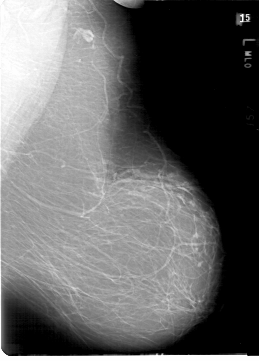

D_4190_1.LEFT_MLO

D_4190_1.LEFT_CC